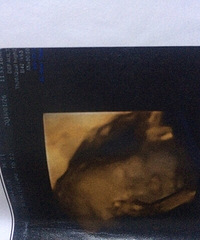

每次洗头都这么一大把

生完孩子3个多月了,现在是纯母乳,洗头发是一把一把滴掉,感觉我的发际线都有点秃了,好担心这样下去会变成秃子啊!!!!!大家有没有好的办法额?这